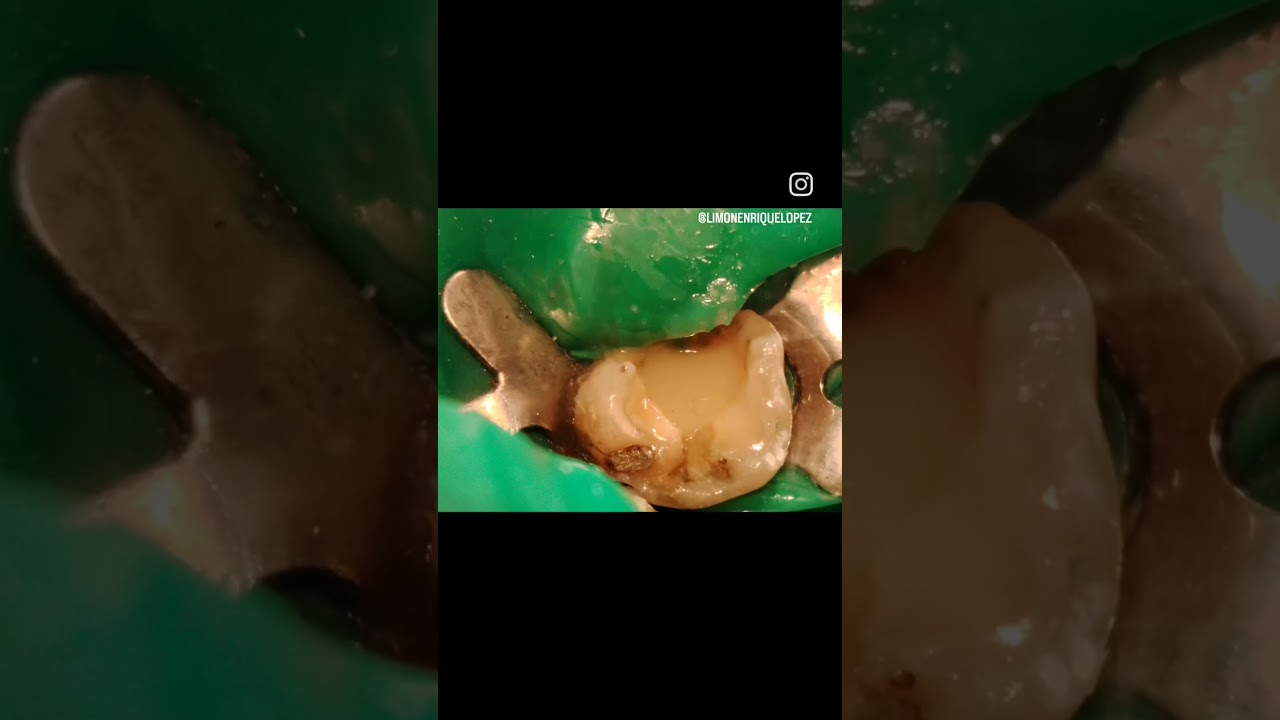

: ¿Sientes un dolor insoportable al tomar algo frío?

Si cada vez que tomas agua fría o comes un helado sientes un dolor agudo, podría ser señal de:

- Caries profunda que afecta el nervio

- Infección en el diente

- Problema en una restauración antigua

• Endodoncia